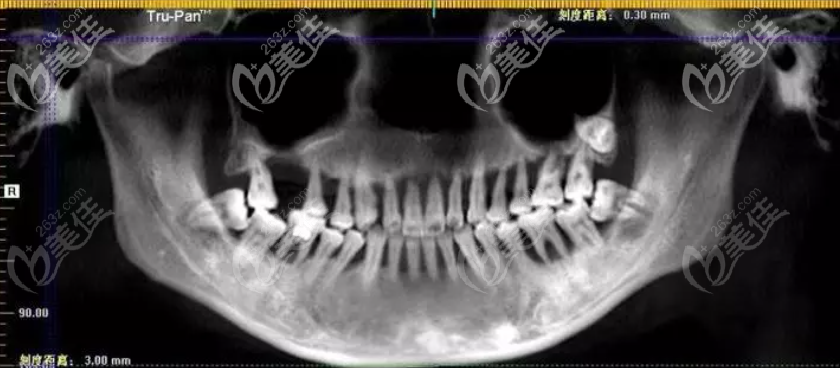

據(jù)了解,這位網(wǎng)友的牙齒大部分有不同程度的松動(dòng),已逐漸喪失了咀嚼功能,一日三餐只能吃點(diǎn)軟的東西,偶爾嘴饞時(shí)喝點(diǎn)肉湯或是吞塊肉,早已不知道吃肉是什么味道。

而導(dǎo)致她牙松動(dòng)及功能喪失的是重度牙周炎,明明才22歲,但你說(shuō)她80歲,或者90歲都不為過(guò);為今后的生活質(zhì)量考慮,她決定為自己做全口種植牙,只要能正常吃飯,多少錢都能接受。